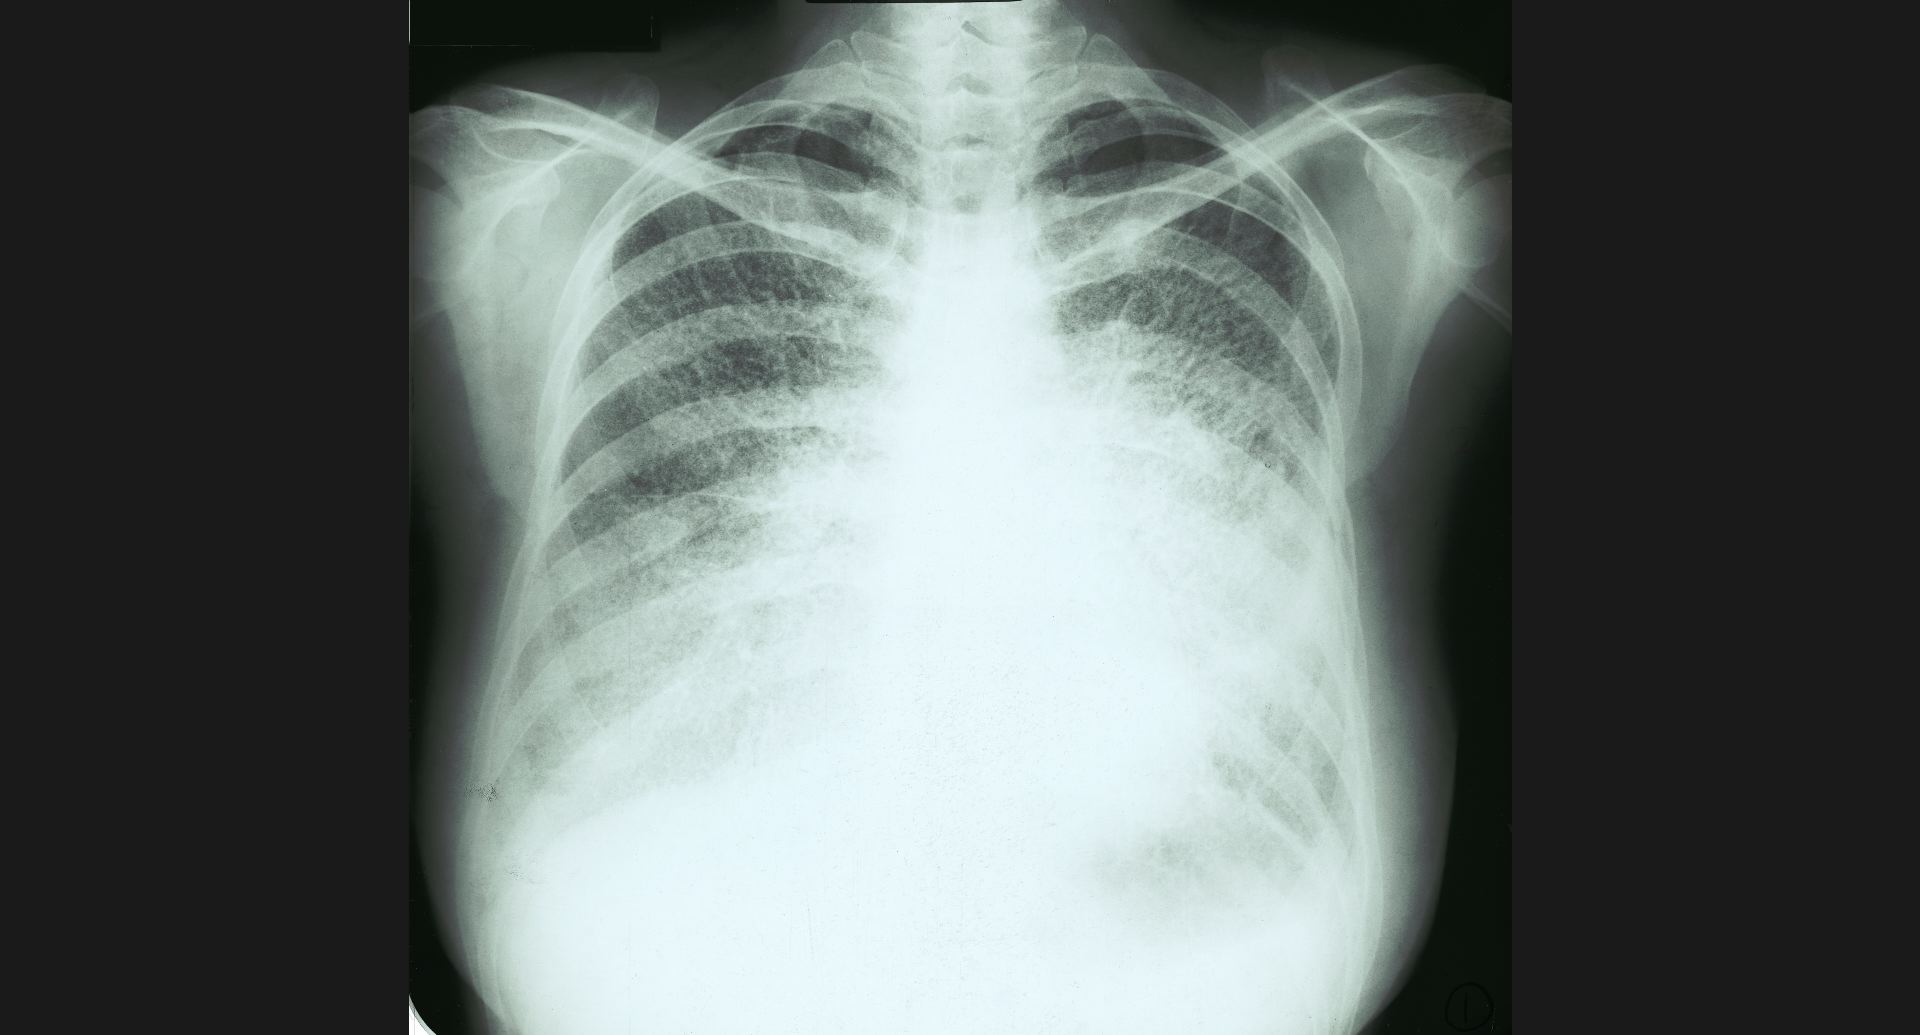

fig.1(117KB) :Alveolar microlithiasis

細かい肺病変、air bronchogram。